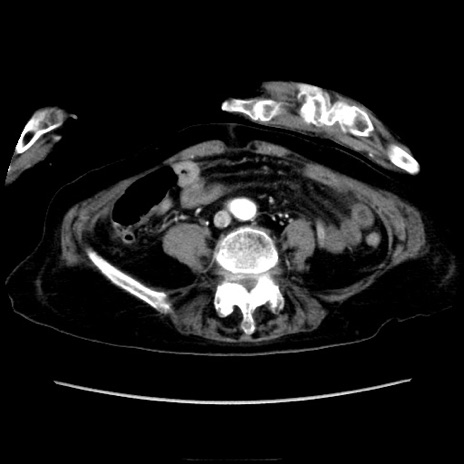

症例40(横断像)

横断像